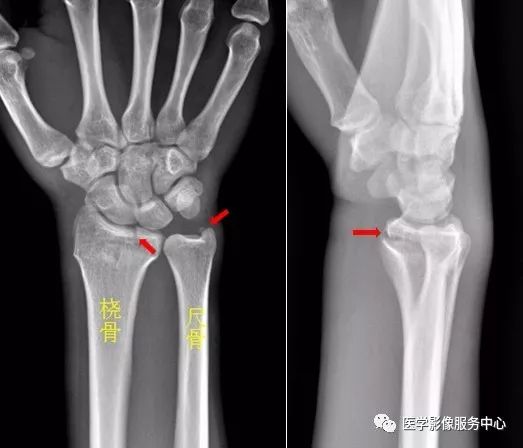

图片

右足第5跖骨基底部见骨折线,断处稍分离移位。右足第5跖骨基底部骨折。

Warmreminder: 儿童时期足第5跖骨处有骨骺存在,骨骺线易与骨折线混淆,小妙招给你,骨骺线的长轴一般是与第5跖骨长轴平行,而第5跖骨多是横行骨折,换言之骨折线与第五跖骨长轴垂直。